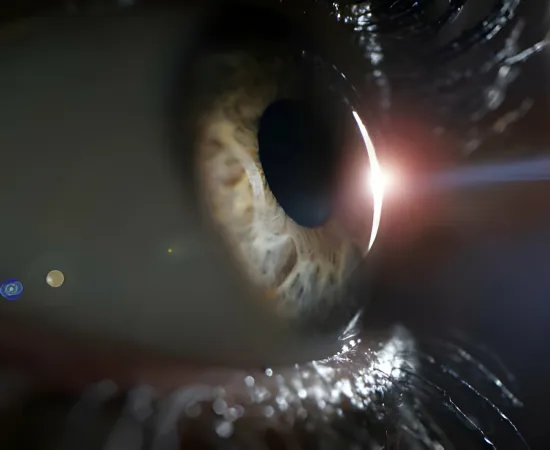

Valeda Işık Terapisi, kuru tip sarı nokta hastalığının tedavisinde kullanılan bir yöntemdir. Bu tedavi, fotobiyomodülasyon (PBM) adı verilen düşük seviyeli ışık terapisi prensibine dayanmaktadır. İşlem, göz dokusuna odaklanan düşük seviyeli ışık enerjisi kullanarak hücresel süreçleri etkileyerek tedavi edici bir etki sağlar. Valeda tedavisi, non-invaziv ve ağrısız bir tedavi yöntemidir. Bu tedavi, retina dokusunu hedef alarak gözdeki hasarı azaltmaya ve hastalığın ilerlemesini yavaşlatmaya yardımcı olur. Aynı zamanda retina dokusunu güçlendirerek görme fonksiyonunu korumayı amaçlar. Valeda ışık tedavisi, katarakt hastalığının tedavisinde de kullanılabilir.

Fotobiyomodülasyon (PBM), düşük seviyeli ışık terapisi veya soğuk lazer tedavisi olarak da bilinir. Hücresel düzeyde biyolojik reaksiyonları tetikleyerek doku iyileşmesini teşvik eden bir tedavi yöntemidir. Hastaların görmelerini artırır ve ayrıntılı görme dahil genel görme fonksiyonlarını iyileştirir. Druzen dediğimiz zararlı retina birikimlerini azaltır. Tedaviler, 3 haftalık bir dönem boyunca, haftada 3 kez, her bir göz için 9 seanslık bir dizi halinde uygulanır. Tedavi seansları her bir göz için 5 dakikadan daha az sürer.

Kuru tip sarı nokta hastalığı, makula adı verilen gözün merkezi kısmındaki sarı noktada (retina) yaşanan dejeneratif bir durumdur. Bu hastalık genellikle yaşla birlikte gelişir ve ilerler. Kuru tip sarı nokta hastalığı, görsel keskinlik kaybına, merkezi görme alanında bozulmaya ve renk algısında sorunlara neden olabilir. Retinanın makula bölgesindeki hücresel hasar nedeniyle oluşur ve genellikle drusen adı verilen sarımsı lekelerin birikmesiyle başlar.